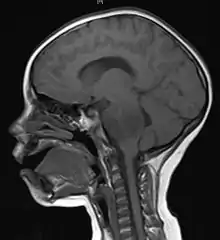

Anatomy

- Brainstem Glioma